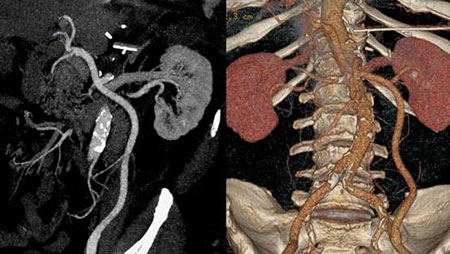

- Conventionally, images were obtained slice by slice sequentially but with multidetector-CT in the spiral mode, large volumes of the body can be scanned rapidly and accurately. The digital information for the scanner is converted to images that can be viewed in any 3D orientation.

- The 16-Slice CT Scanner captures multiple images of a patient’s anatomy in a matter of seconds and presents information 3-dimensionally. This means the images of the body are now taken much faster, therefore reducing the examination time and increasing your comfort.

- The information provided is more detailed due to the ability of the scanner to produce thin-slice images; this allows early detection of certain diseases in a less invasive manner.

- CT Angiography